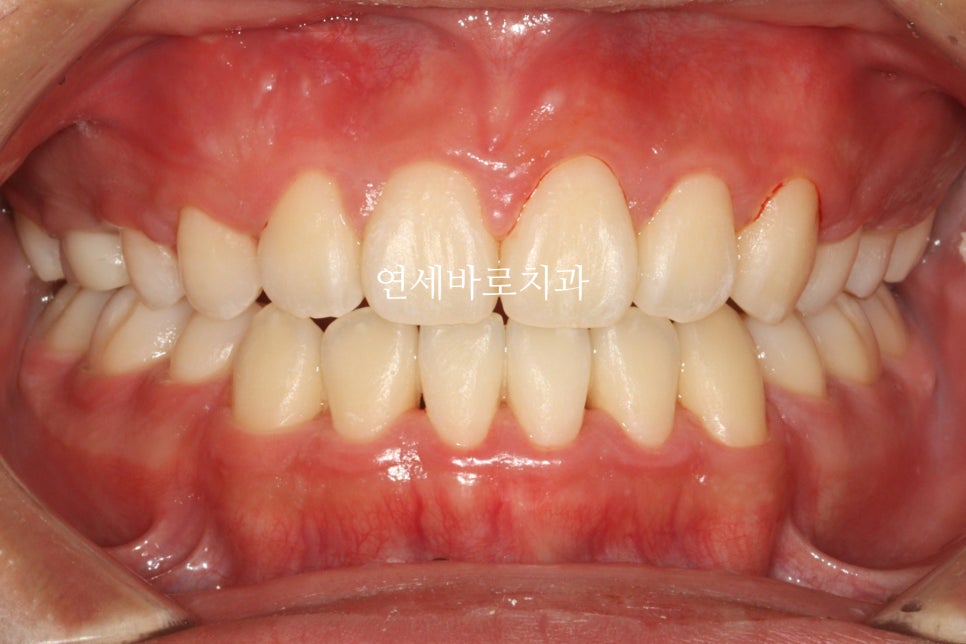

그리고 24.6. 교정을 시작한지 약 1년 반정도만에 치료가 마무리 되었습니다.

송곳니를 발치함으로 얻은 이득 중 하나는 '치료기간'입니다.

치료기간이 엄청 짧아진거죠.

단점은 좌우 대칭이 아니라 약간의 심미적인 문제가 생기는 것입니다.

그 심미적 문제가 이것입니다.

화면의 왼쪽은 작은 어금니

오른쪽은 송곳니 입니다.

그래서 모양이 다르죠.

이런문제가 있긴 하지만 거의 티가 나진 않습니다.

이렇게 보니 차이가 조금 더 크죠?

이런 문제가 있지만 송곳니 발치는 종종 선택되어 집니다.

전과 후를 비교하며 작성을 마치겠습니다.